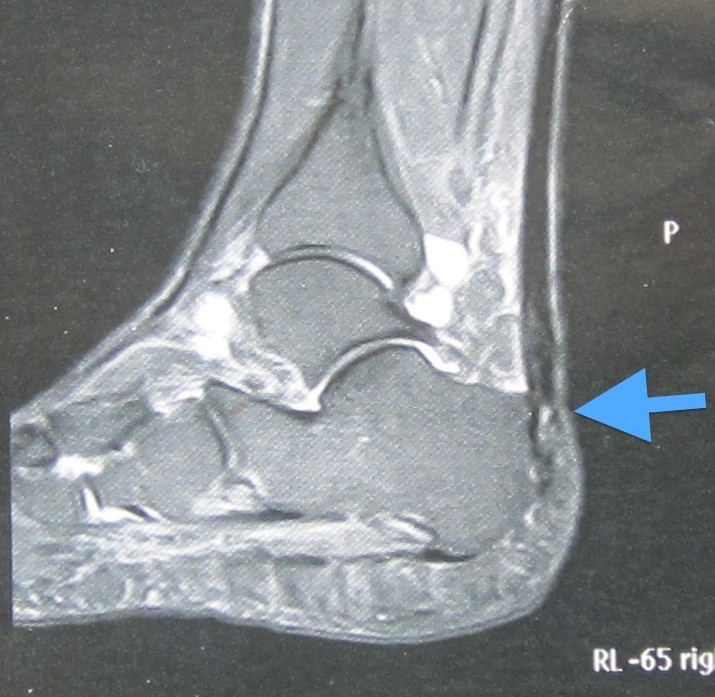

Im Röntgen und in der MRT sieht man, dass ein Knochenstück mit abgerissen ist. Die Ursache war ein oberer Fersensporn, der abbrach. Die andernorts durchgeführte konservative Behandlung wurde von uns sofort eingestellt und die Patientin operiert:

Links: Mehr als die Hälfte der Achillessehne ist mitsamt dem oberen Fersensporn abgerissen - Pfeil.